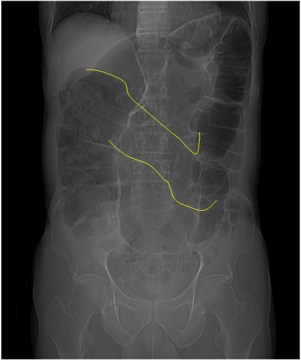

SIGNO DEL PICO

Signo de vólvulo y otras causas de obstrucción intestinal en asa cerrada, que inicialmente se describió en el estudio baritado (enema opaco). Se refiere a la estenosis fusiforme que se dirige al punto de torsión (flecha roja en la radiografía y flecha negra en el esquema). En caso de que el contraste atraviese la estenosis y exista una disminución de la luz en el segmento proximal de la torsión, la imagen obtenida recuerda a la de dos pájaros con sus picos juntos.

La imagen muestran el Signo del pico en un paciente con un vólvulo de sigma.

Aunque lo hemos incluido dentro de los signos de colon, este signo también es visible en las obstrucciones en asa cerrada de intestino delgado.

Inicialmente descrito en el enema opaco, en la TC también es visible este signo y no solamente en el asa eferente (como ocurre en el enema opaco, donde este asa se rellena retrógradamente) sino también en el aferente.